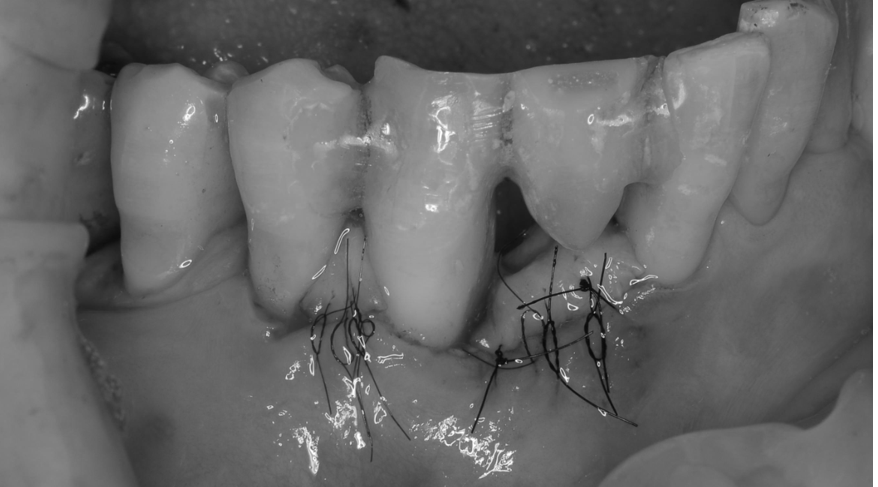

歯科ドックを行い、総合的な観点から判断し、歯周基本治療と

再生療法を行い

昨日の検査で数値が健康に戻りました!!